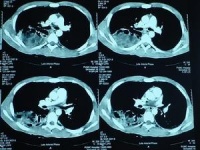

1.X 线检查 X 线钡餐透视或气钡双重造影,可发现钡剂在胃内产生分流现象,并显示浮于钡剂上层游离性、团块状、圆形或椭圆形充盈缺损区,而胃黏膜结构光整,胃壁柔软。当胃内钡剂排空后仍可见团块影上有条索状、网状或片状钡斑黏附。按压团块阴影无明显压痛,并可随力度而改变轮廓形态及位置,提示结块有一定压缩性、游走性。

2.纤维内镜检查 纤维内镜下可直视观察胃内结石的形态、性状等。植物性胃石因结块成分不同,可呈黄色、棕色、褐色或绿色,常为圆形、椭圆形的单个或多个游离团块。毛胃石一般为黑色或棕褐色,呈“J”形或肾形,可充满胃体或伸入十二指肠。纤维内镜还可了解胃部有否合并胃炎溃疡病等其他征象,必要时还可钳取结块成分或并发症的胃组织进行分析。因此。有条件的医院疑胃石症者应把纤维内镜检查作为首选的诊断手段。

3.B 超检查 B 超对胃石诊断有一定帮助。通常嘱患者饮水500~1000ml,坐位或半卧位检查,可见到胃内有界限清晰的强回声团块影像,浮于水上层,并可随体位变化或胃的蠕动而改变位置。